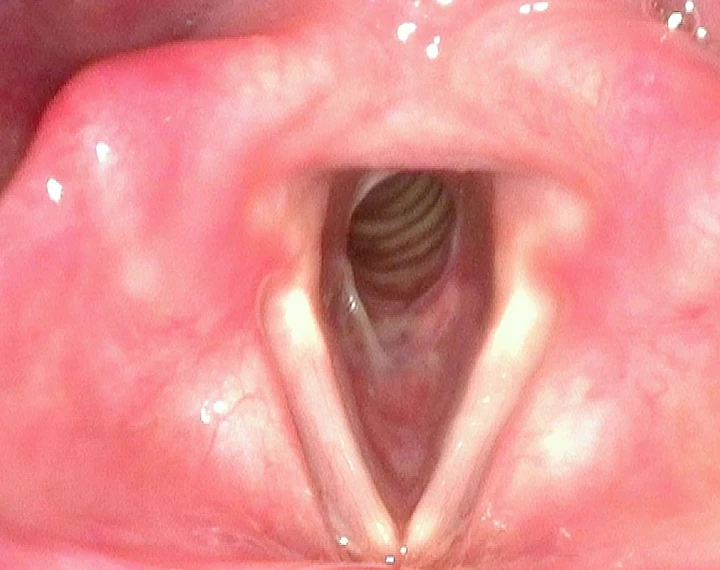

Image Sequence

- After 5 years of multiple endoscopic treatments the patient was referred with acute airway distress. The subglottic airway was 4mm (normal 12-20mm).

- Following endoscopic treatment the airway was much improved. The patient required repeated procedures and lived in a rural location.

- The patient proceeded with a cricotracheal resection and this image is 18 months post surgery